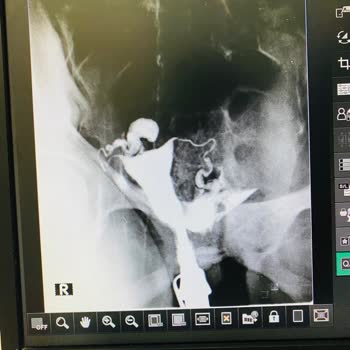

02.07.2024 de annemi şiddetli karın ağrısı şikayetiyle Konya medova Hastanesi genel cerrahi bölümüne götürdük. Dr. H*** m***** ç**** muayenesini yaptıktan sonra bağırsak düğümlenmesi olduğunu söyleyip acil ameliyat gerektiğini, fiyat için ilgili bölümle görüşmemizi söyledi. Fiyatlandırma bölümüne gi...